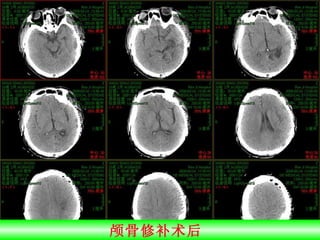

颅骨修补

颅骨修补术后

例 2  男性 32 岁,修补术后 CT